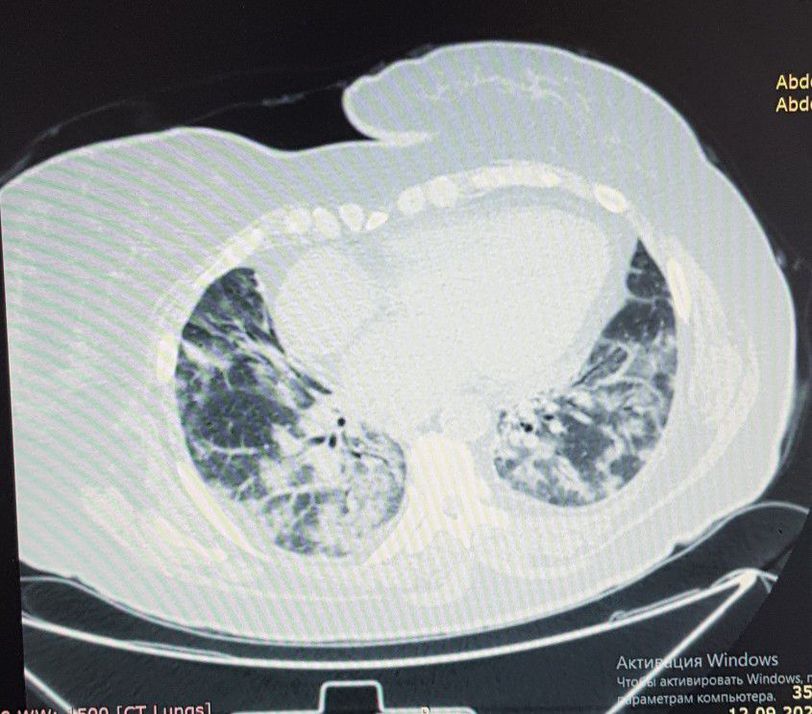

COVID-19 TORAX CT

Infection

Ct

Coronavirus

Pneumonia